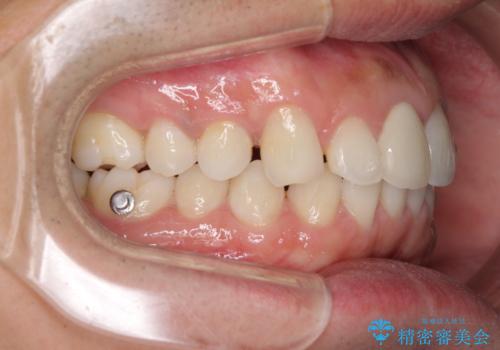

- 口の閉じにくさを気にして来院された患者様です。

患者様と相談の上、横顔の印象から抜歯矯正は必要ないと判断し、IPR(歯と歯の間)並びに歯列全体の後方移動により口元の突出感の改善することとしました。

しっかりと装着時間を守り、ゴムかけも徹底していただいたので、思いの外口元を引っ込めることができました。

これ以上の改善を望まれましたが、非抜歯矯正でこれ以上口元を引っ込めると食いしばりすやすい咬合となるため、この歯列で終了としました。